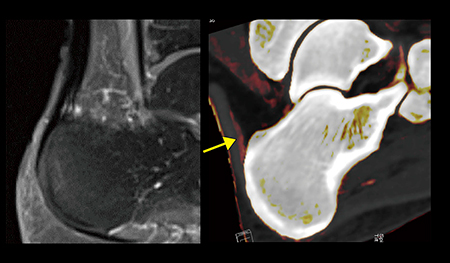

症例3は30歳代,女性。乾癬歴4年で,アキレス腱の痛みを訴えていた。造影MRIでは診断を確定できず,DECTを撮影したところ,ヨードマップ画像ではアキレス腱に沿って造影効果が認められ(図6 →),PsAによるアキレス腱の付着部炎と診断できた。

図6 症例3:PsA(30歳代,女性,乾癬歴4年)